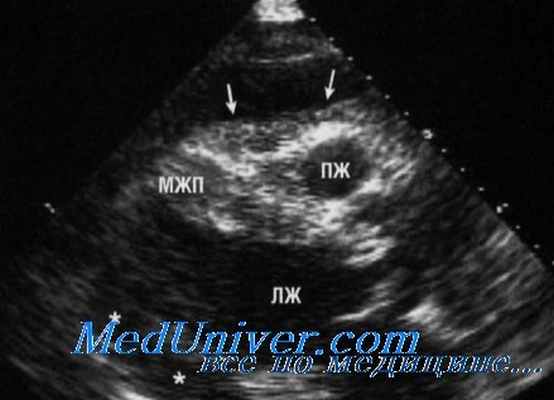

Характерная находка на рентгенограмме грудной клетки - округлая, четко очерченная рентгеноконтрастное образование под правым кардио-диафрагмальным углом, прилегающая к диафрагме. Сообщалось о других местах, таких как левый сердечно-диафрагмальный угол или где-либо еще в верхнем средостении. На эхокардиографии они выглядят как локализованное свободное от эхонегативное пространство, прилегающее к границе сердца, чаще всего около правого предсердия. Они могут исказить нормальную форму предсердия. При эхокардиографии киста выявляется как округлая эхонегативная кистозная структура, прилегающая к правому предсердию или желудочку, которая не сообщается с перикардиальным пространством. Чреспищеводная эхокардиография может дать лучшее определение ее размерам. Большие кисты перикарда могут привести к сдавлению правой камеры сердца и появлению симптомов. Цветное допплеровское картирование и импульсный допплеровский спектр при настройках на низкой скорости можно использовать, чтобы гарантировать отсутствие фазового потока внутри образования.

На УЗИ кисты перикарда необходимо дифференцировать от локализованного выпота в перикарде, увеличения камеры сердца, диафрагмальной грыжи и злокачественных опухолей. Двумерная эхокардиография может легко отличить анэхогенное содержимое перикардиальной кисты от солидных структур. Типичное расположение кист перикарда в правом сердечно-диафрагмальном угле является еще одним ключом к разгадке, хотя они также могут быть обнаружены в левом сердечно-диафрагмальном углу, воротах и верхнем средостении.

В марте 2012 г. выполнена селективная ангиография коронарных артерий, по результатам которой гемодинамически значимых сужений коронарных артерий выявлено не было. По результатам иммунологического исследования данных, свидетельствующих о миокардите, не получено. По данным эхокардиографии выявлена инкапсулированная полость (киста перикарда?), деформирующая правое предсердие, правый желудочек, размерами 3,5×6 см. Левый желудочек: толщина межжелудочковой перегородки (диаст.) – 1,1 см, толщина задней стенки левого желудочка (диаст.) – 0,8 см, конечный систолический размер – 3,5 см, конечный диастолический размер – 5,3 см, конечный диастолический объем – 133 мл, конечный систолический объем – 51 мл, ударный объем – 82 мл, фракция выброса (по Тейхольцу) – 62%. Левое предсердие: диаметр – 3,5 см. Митральный клапан: не изменен, движение створок разнонаправленное, диаметр фиброзного кольца – 2,7 см. Аортальный клапан: не изменен, диметр фиброзного кольца – 2,4 см. Аорта: диаметр на уровне синуса Вальсальвы – 3,7 см; диаметр восходящего отдела – 3,8 см. Трикуспидальный клапан: не изменен, диаметр фиброзного кольца – 3,5 см.